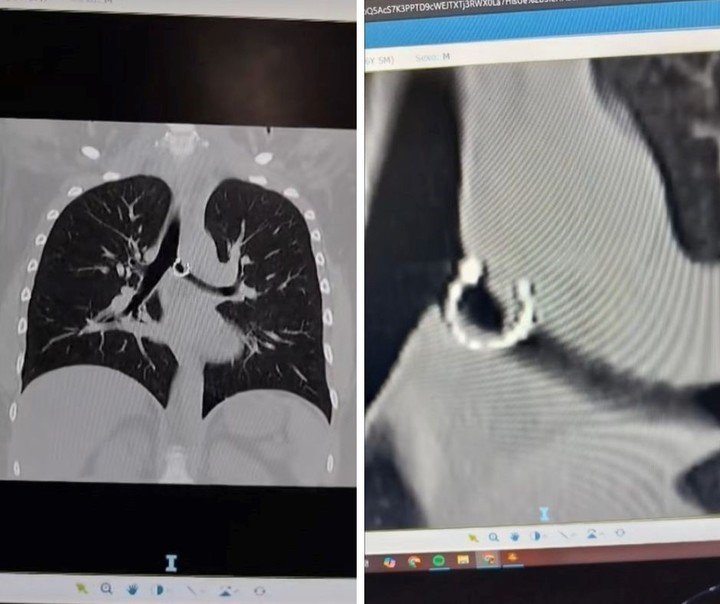

«Los médicos estaban impactados», dijo en las redes sociales una joven sobre el presunto hallazgo que hicieron dentro de su cuerpo. Según explicó, en un hospital descubrieron que su piercing nasal, que había perdido, se encontraba en uno de sus pulmones.

A través de este posteo, visto por más de cuatro millones de personas, aseguró haber aspirado un aro que llevaba en su nariz sin darse cuenta —lo hizo mientras dormía—, lo que le causó problemas de salud. Además, mostró radiografías e imágenes de la pieza de joyería.

«Ahorita me río, pero en el momento fue un horror. Los médicos estaban impactados, así como yo y todos a mi alrededor», escribió el 7 de diciembre la joven, quien, de acuerdo con el portal de noticias Need To Know, tiene 26 años y es de México.